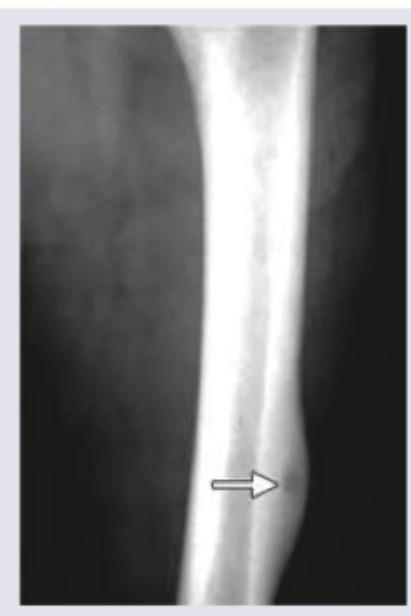

97. Spot the diagnosis based on X-ray:

Explanation: ***Osteoid osteoma*** - The X-ray image shows a small, well-defined **radiolucent nidus** (indicated by the arrow) surrounded by a significant amount of **sclerotic bone reaction**. This appearance is characteristic of an osteoid osteoma. - The nidus, which contains osteoid tissue, is typically less than 1.5 cm in diameter and is the source of the pain, often relieved by NSAIDs. *Osteochondroma/exostosis* - An osteochondroma is a **bony projection** covered with a cartilaginous cap that arises from the external surface of a bone, usually near a growth plate. - It would appear as a clearly defined, sessile or pedunculated outgrowth from the cortex, which is not what is seen here. *Ewing's sarcoma* - Ewing's sarcoma is an aggressive malignant tumor characterized by a **permeative or moth-eaten osteolytic pattern** and often an **"onion-skin" periosteal reaction**. - It does not typically present with a small, central nidus surrounded by dense sclerosis like an osteoid osteoma. *Osteosarcoma* - Osteosarcoma is also a highly malignant bone tumor, often characterized by **sclerotic and lytic areas**, a **Codman triangle**, or a **sunburst appearance** due to aggressive periosteal reaction. - The image does not show these features; instead, it presents with a focal nidus and organized sclerosis, typical of a benign process.